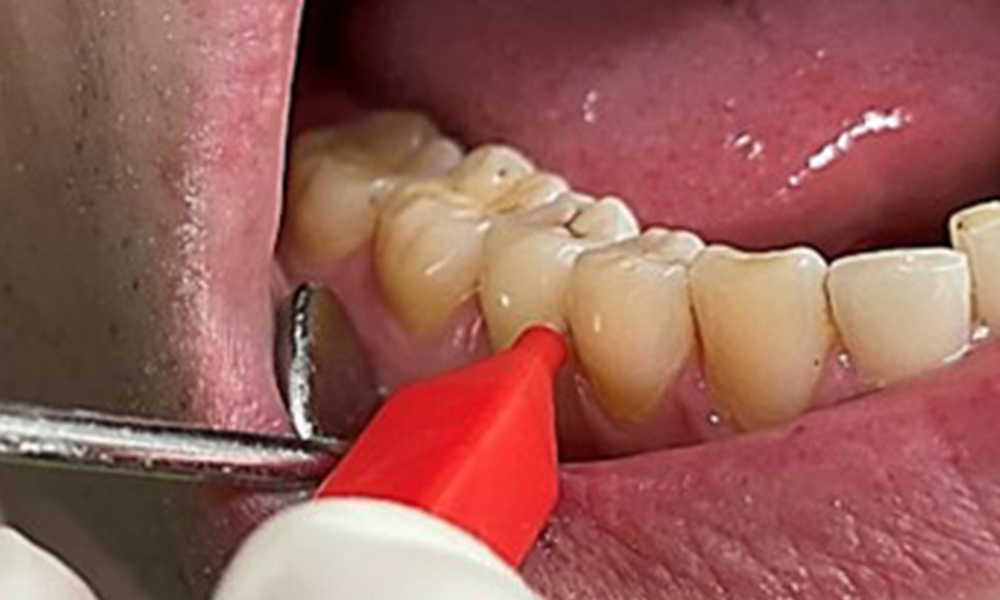

Due to the otherwise favourable general medical condition, the needs determined during the intraoral examination will be decisive for their treatment. It will be essential to periodically determine the probing depths. Gingival bleeding decreases in smokers, which is why the clinical diagnosis of periodontitis can only be made by probing (Fig. 7). Placing exclusive focus on the determination of bleeding indices may obscure existing periodontitis or gingivitis. (5)

- It is important to document findings during the therapeutic appointment. Bleeding-on-probing (BOP) status to measure periodontal pocket depth in the early stages of disease must be determined during each appointment. This is particularly important in smokers due to decreased tissue perfusion.